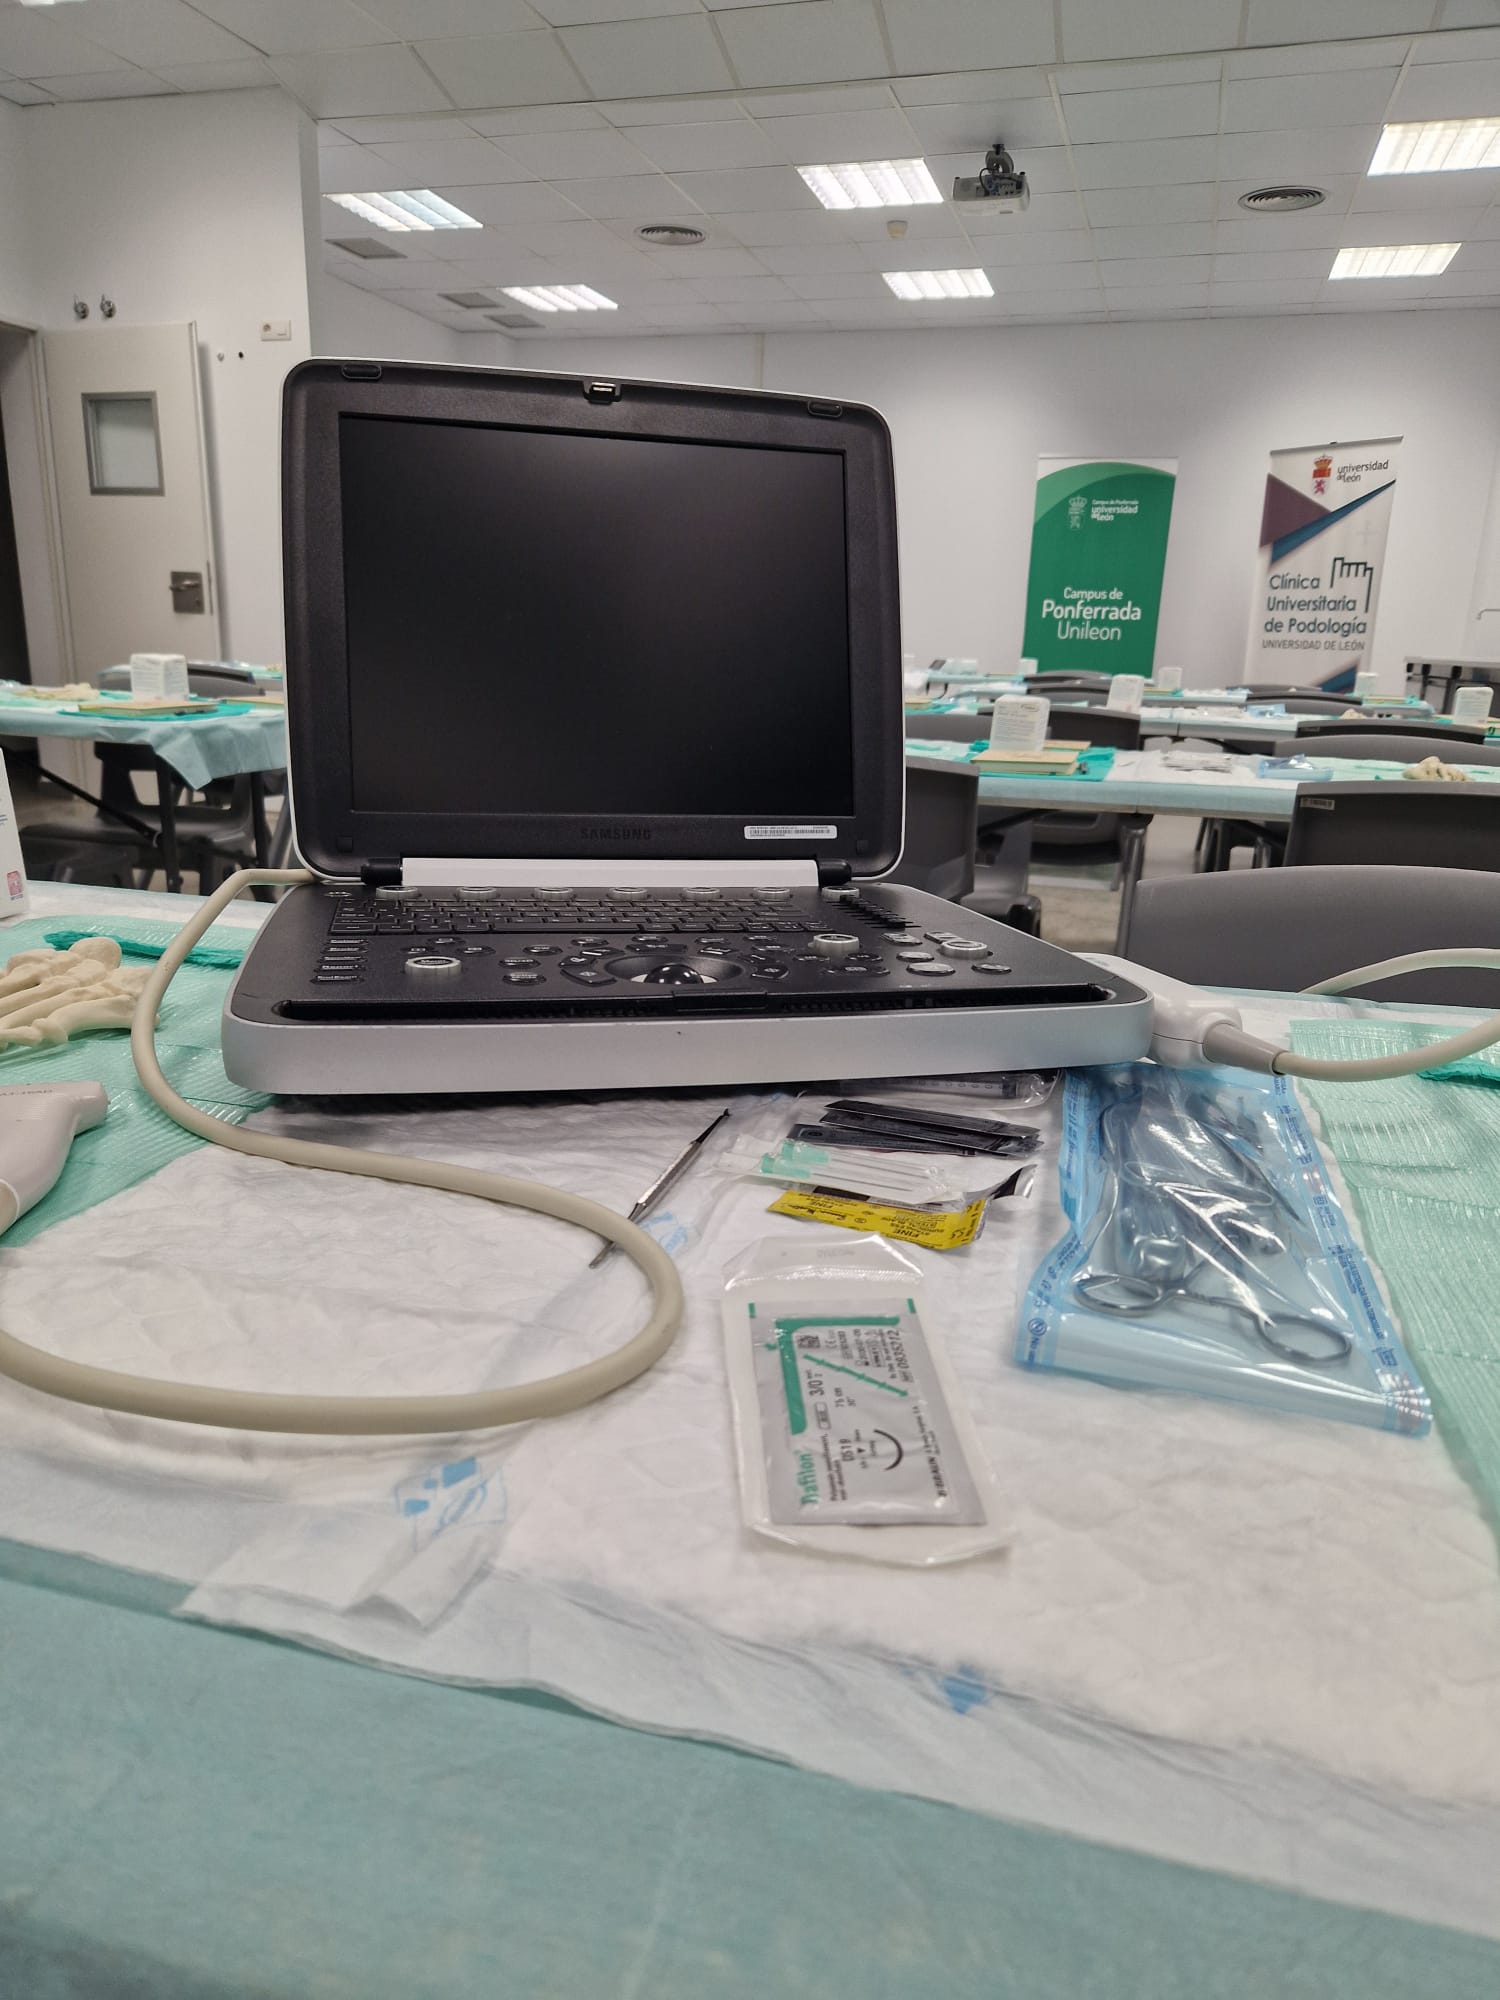

Samsung HM70A Plus

Samsung HM70A Plus

- El ecógrafo Samsung HM70 EVO es un dispositivo portátil de alto desempeño, diseñado para cubrir una amplia variedad de aplicaciones clínicas y adaptarse a distintos tipos de pacientes. Cuenta con un flujo de trabajo eficiente, gran resistencia y una calidad de imagen de alta definición, lo que permite su uso en múltiples entornos y escenarios clínicos.

- Envío Incluido a España Peninsular.